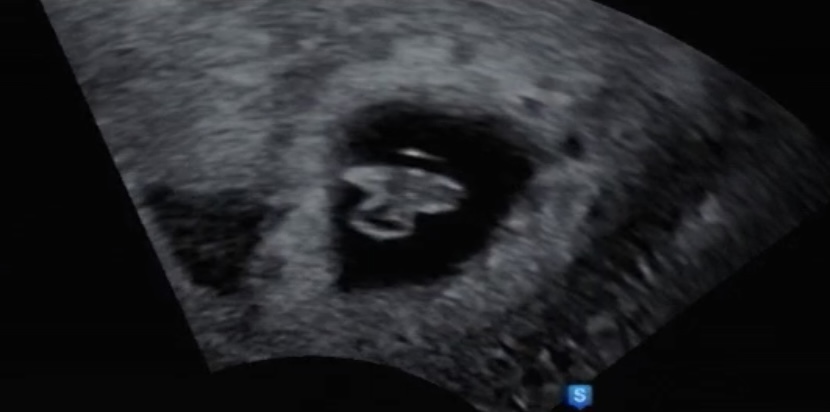

임신 5주차, 임신테스트기로 임신이 되었다는 것을 확인하고 그 다음주에 병원에 가서 아기집을 확인했다. 아기집을 확인한게 임신 6주차 였고 그 때부터 입덧이 기운으 스멀스멀 올라왔던 것 같다. 7주차에가니 그난황과 난황에 붙어있는 아기세포를 보았다. 일명 다이아몬드링. 넌 내 안에 있는 소중한 보석이구나 하고 생각했다. 그것도 알맹이가 아주 큰! 아 그리고 같은 날 심장소리도 들었다. 쿵 쿵 쿵 쿵 힘차고 빠르게 뛰던 너의 심장소리는 평생 잊지 못할 것 같아! 8주차를 건너띄고 9주차에 만난 꼬물이. 나는 이 날 젤리곰을 만났다! 귀여워 ‘나는 입덧때문에 힘든데 넌 잘 크고 있구나’ 임신 초기엔 병원을 2주,3주 간격으로 가니 시간이 정말 안가는 것 처럼 느껴졌다. 게다가 입덧때문에 하루종일 속도 안좋으..